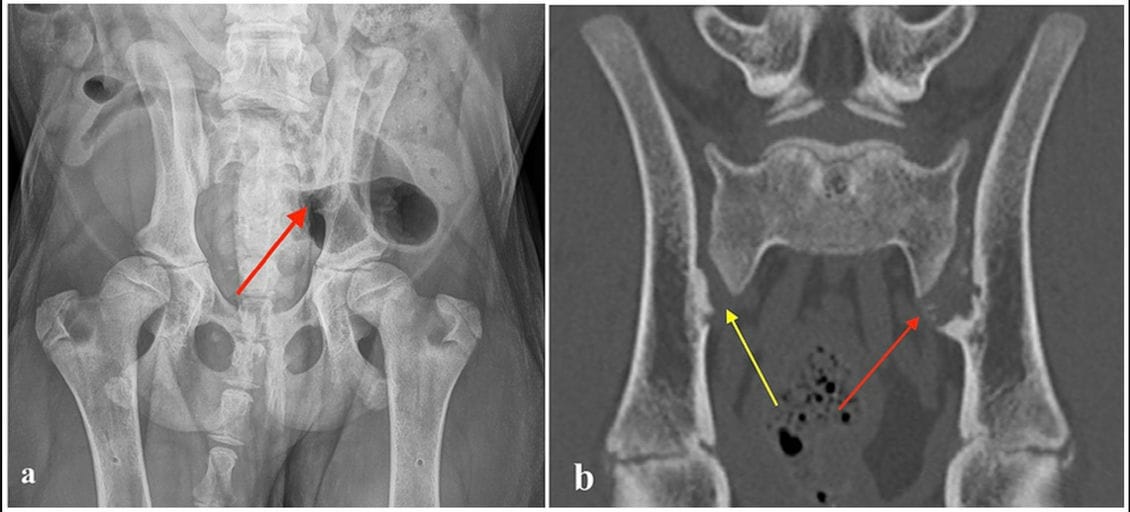

(a) Ventrodorsal radiograph of a four-month-old Bernese Mountain Dog with erosive lesions in the left sacroiliac joint (red arrow). (b) Computed tomography image (coronal plane) of the same dog, showing multiple small, randomly distributed cystoid and irregularly shaped concave defects within the left sacroiliac joint surface with deep peripheral sclerosis (left side red arrow). Similar but milder defects are visible on the right side (yellow arrow).

Initial radiographs and CT revealed bilateral erosive lesions of the sacroiliac joints, more severe on the left side, characterized by multiple articular bone erosions, peripheral sclerosis, and joint space widening. Clinical signs resolved rapidly within weeks of conservative treatment. Follow-up radiographs at 6 weeks showed partial resolution of erosive changes, and by 1.5 years, both radiography and CT demonstrated complete resolution of SIJ lesions. The dog remained clinically normal throughout long-term follow-up despite concurrent moderate hip dysplasia.